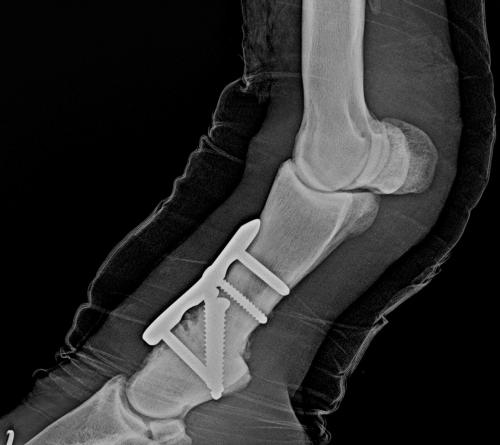

A pre-surgical consultation is important so you fully understand the reason your horse requires surgery and to establish what steps are necessary prior to and after the procedure. During this consultation, results of lameness examination and diagnostic imaging are discussed so it is important to provide these to the surgeon ahead of time if they were performed by your regular vet. Sometimes one or more of these studies will need to be repeated, if sufficient time has elapsed between the original study and the surgery date.

A rehabilitation program will be provided for your horse. This may also include suggestions for post-surgical treatments. For example, it is routine to perform Hyaluronic acid/corticosteroid injections at 2 weeks post surgery following arthroscopic chip/fragment removal. When there is substantial soft-tissue or cartilage injury, we often recommend biologic therapies.